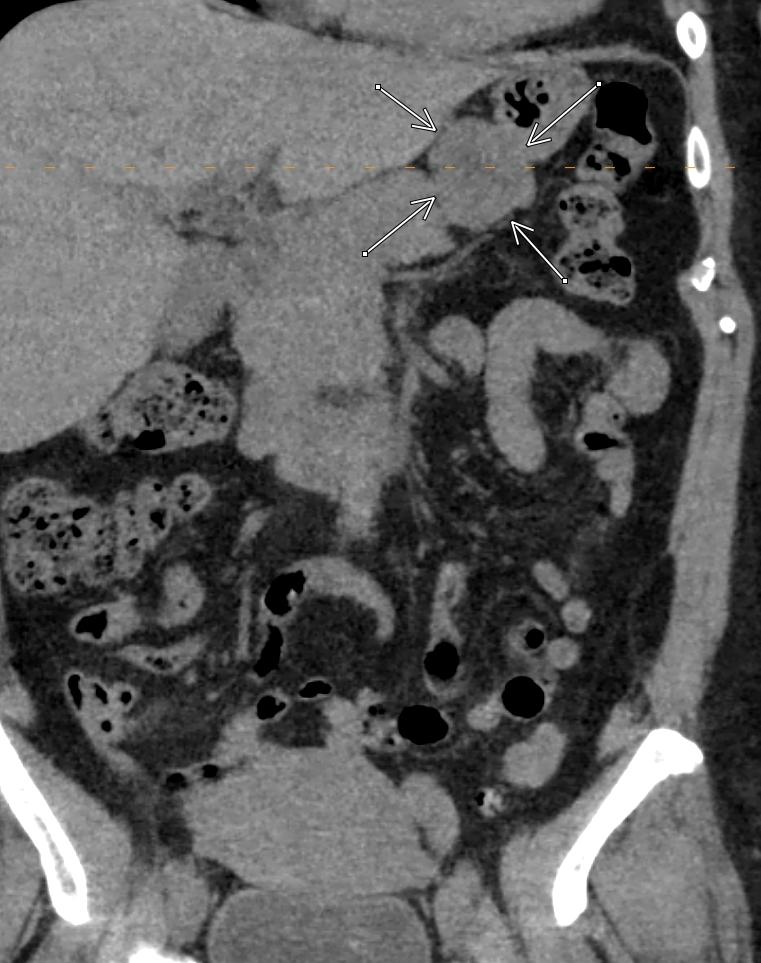

Non displaced trabecular compression fractures are

#easytomiss in osteoporotic#spine;#radres please review soft tissue window for such fractures-surrounding sclerosis due to edema/hemorrhage/compression can make them more visible#FOAMed@NASSspine https://bit.ly/37XAAdH pic.twitter.com/1oGrDA6jz6